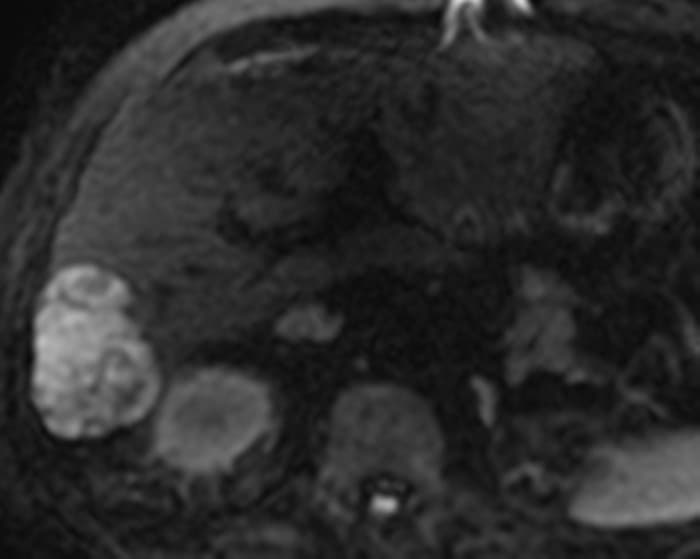

U máu gan

» Thông tin: Nam giới – 70 tuổi.

» Lâm sàng: Tiền sử ung thư thận.